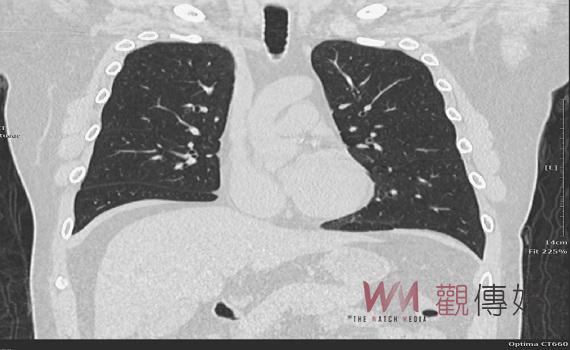

▲臺中榮總埔里分院免費為大埔里地區民眾肺癌篩檢,歡迎多加利用。

(圖/臺中榮總埔里分院提供)

LDCT是目前唯一具國際實證,可以早期發現肺癌的篩檢工具,自費檢查費用平均5千到8千元不等。7月上路的公費篩檢對象,包括「具肺癌家族史」50至74歲男性或45至74歲女性,且其父母、子女或兄弟姊妹經診斷為肺癌之民眾;以及「重度吸菸史」50至74歲吸菸史達30包-年以上,有意願戒菸或戒菸15年內之重度吸菸者。

LDCT檢查過程僅需10分鐘,且檢查前不需禁食和禁水,輻射量僅是傳統電腦斷層的1/5, LDCT篩檢發現結節的比例很高,多數為良性結節,建議檢查結果異常的民眾配合醫師建議持續定期追蹤,以觀察結節有無新增或變化。